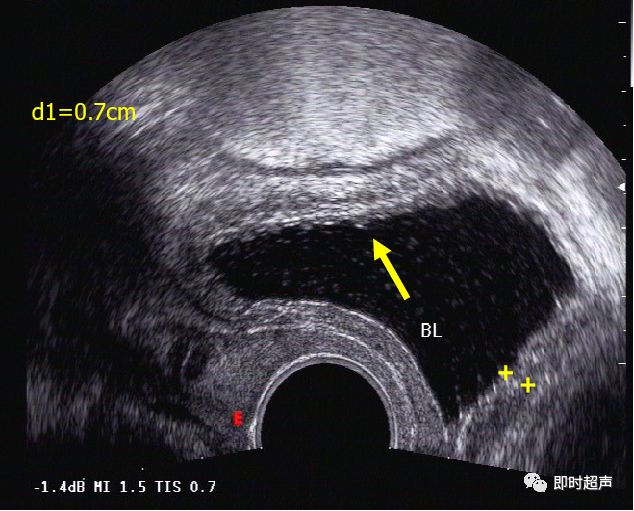

正常膀胱超声图像(经阴探测)

(膀胱壁呈中强回声光带,呈三层结构,分别由黏膜层(含黏膜下层)、肌层、浆膜层(含浆膜下层)组成,厚约0.1cm~0.3cm.膀胱内为无回声液性暗区 。经腔内扫查:能更清晰地显示膀胱壁的三层结构,(如图所示)尤其是检查膀胱后壁及三角区病变)